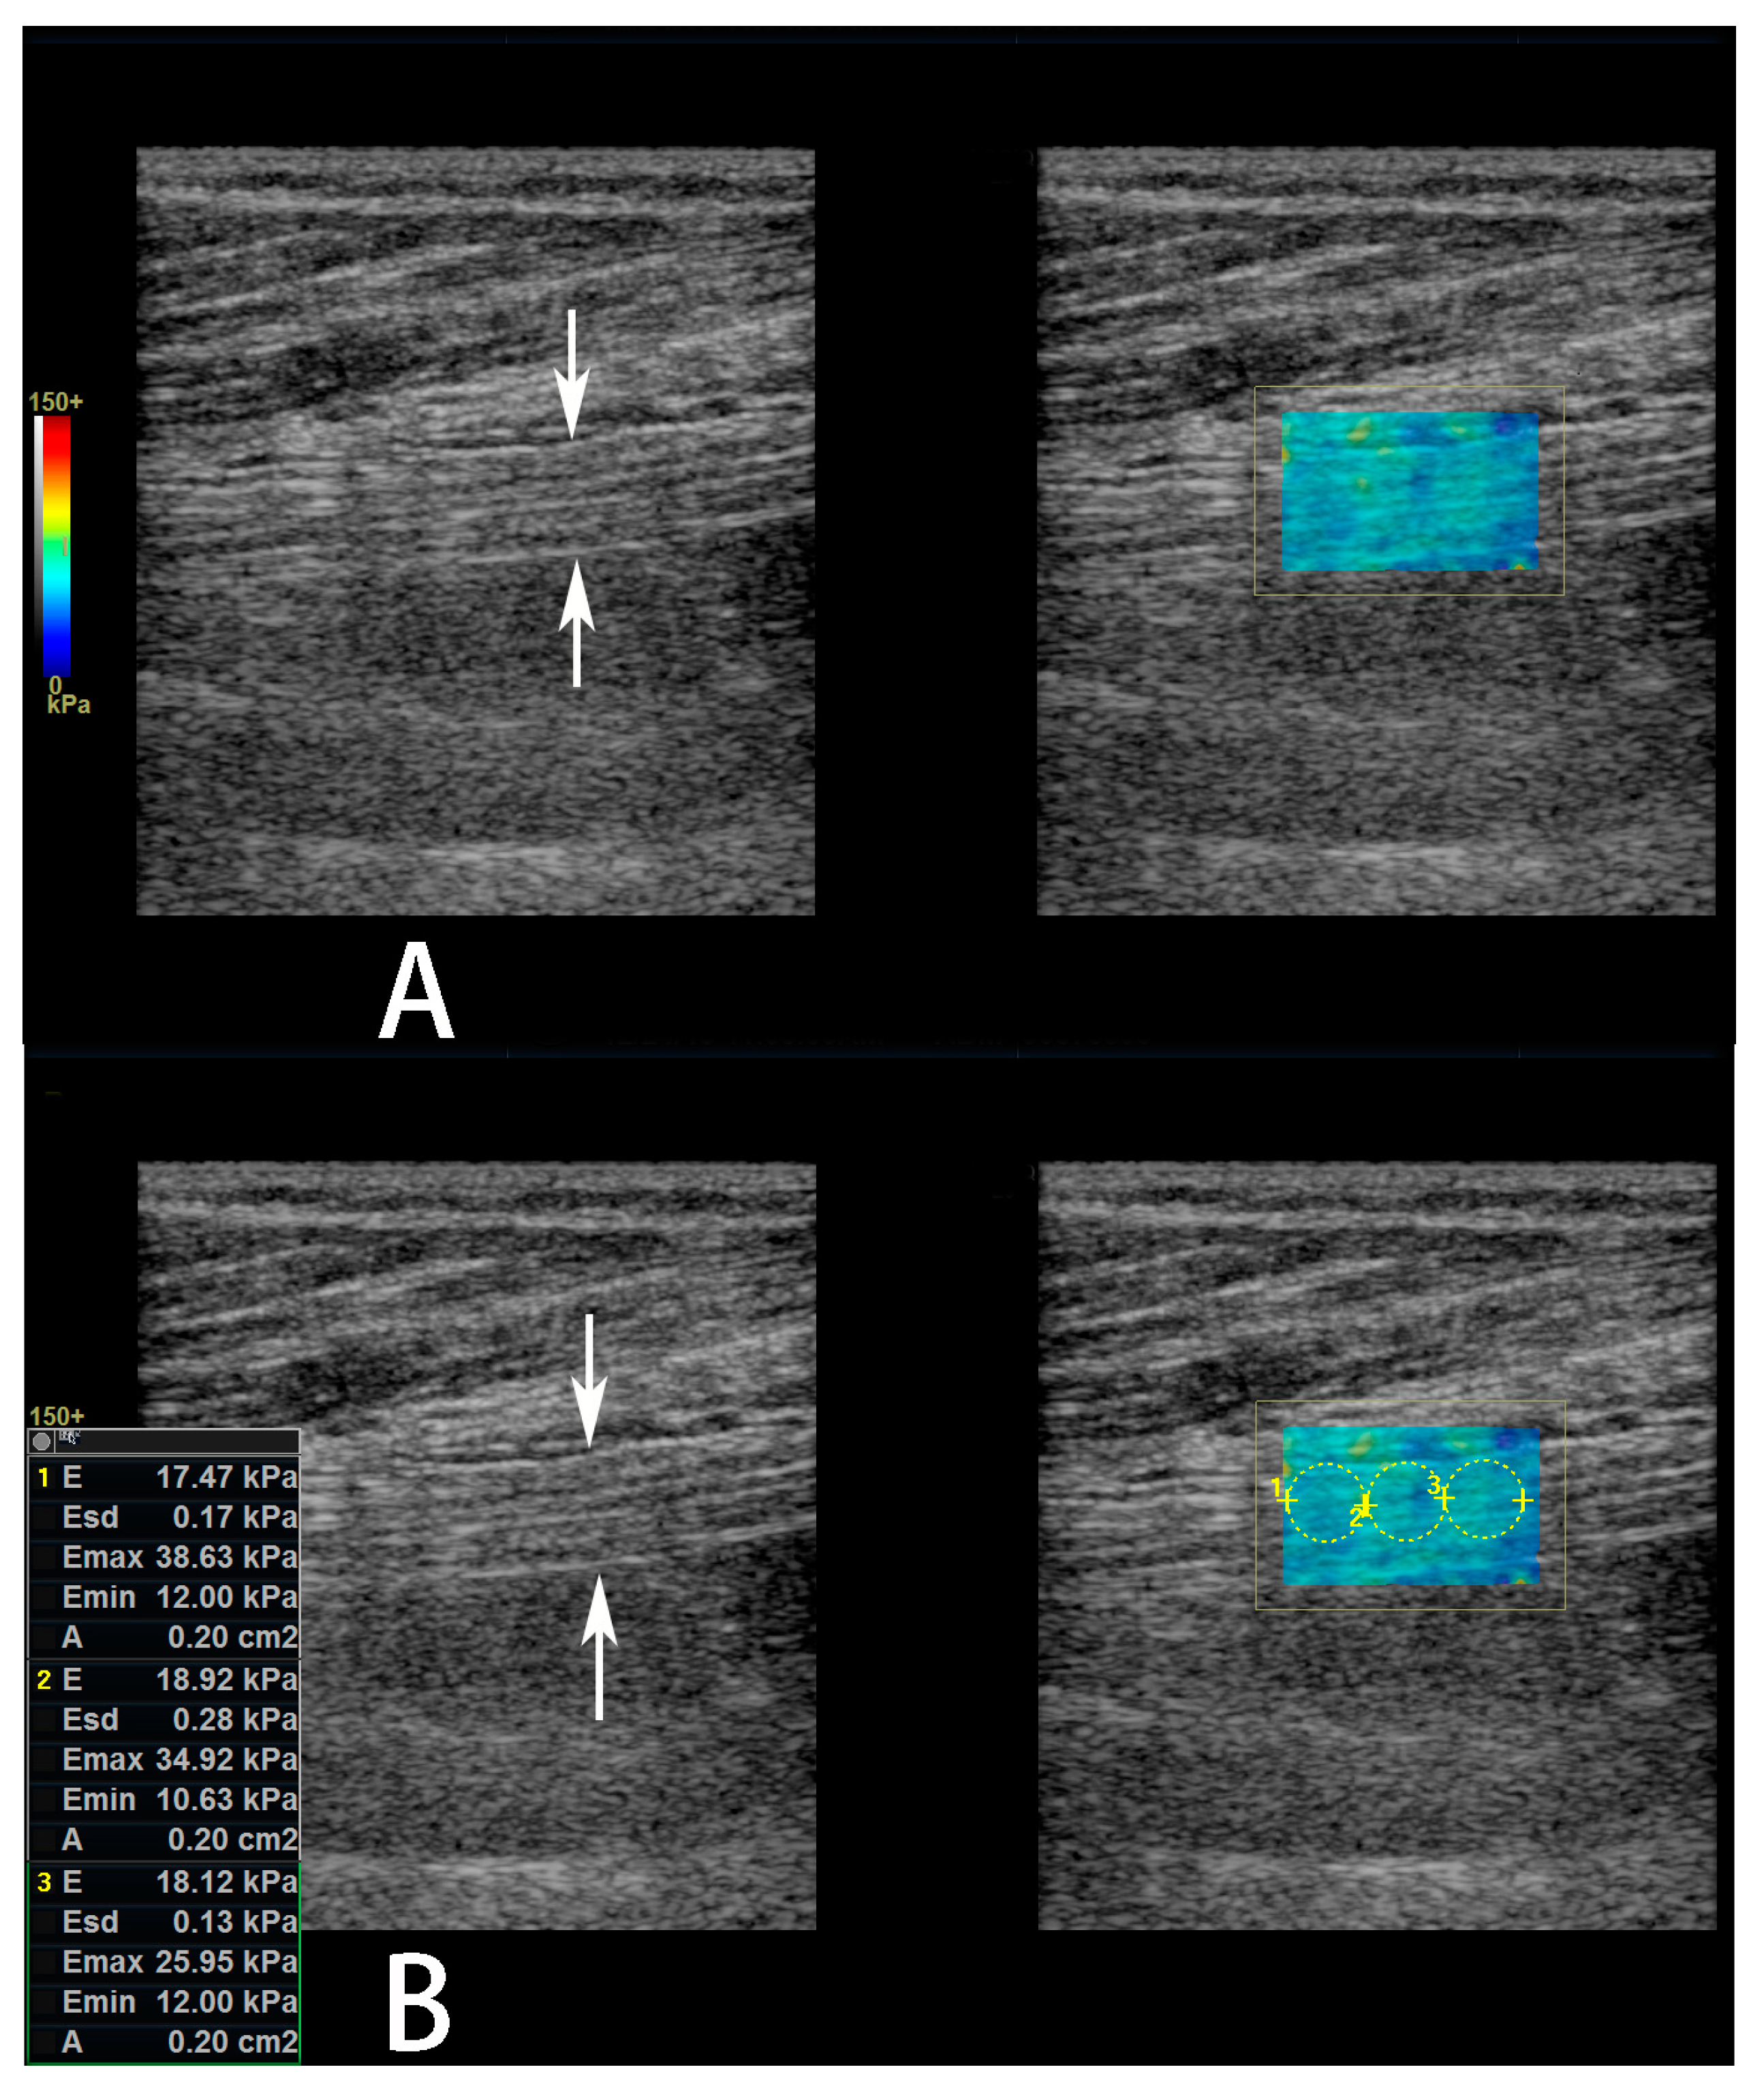

The sonographic parameters of the sciatic nerve were measured at about 3 cm proximal to the bifurcation of the tibial and common fibular nerves. Initially, transverse imaging of the bifurcation of the tibial and common fibular nerves were obtained, and the bifurcation positioned in the centre of the screen. Then, the transducer was rotated 900 to obtain longitudinal imaging of the nerve. Next, the transducer was moved towards the proximal thigh and the bifurcation disappeared on the screen. Lastly, the transducer was re-rotated 900 to obtain transverse imaging of the sciatic nerve. First, the CSA of the nerve was measured on the transverse image using a manual trace directly over the epineurium. Then, power Doppler US was performed in both transverse and longitudinal imaging planes (a parallel orientation to the sciatic nerve fibers) to observe the blood flow within the nerve. If the intraneural blood flow existed, then the spectral Doppler US was performed on the brightest vessels to observe the wave form and measure the velocity (for arteries, the peak systolic velocity (Vmax) and the minimal diastolic velocity (Vmin) were measured) and resistive index (for arteries, RI). The RI was defined as [1 − (Vmin ÷ Vmax)]. Last, SWE was performed in the longitudinal imaging plane. A color-coded box was superimposed on the image, and the size of the acquisition box was kept the same (20 × 14 mm) for all the patients. The spectrum scale of colors ranged from blue for softer tissues to red for stiffer tissues. When the frozen images of the nerves were obtained (probe was held stationary for 3 s), a circular region of interest (ROI) with a diameter of 2–4 mm was placed within the nerve according to the nerve’s diameter to represent the SWE stiffness value measurements. The mean elasticity within the ROI are expressed as the mean of three different measurements, and was reported in kiloPascals (kPa) (Figure 2).

Figure 2.

Measurement of sciatic nerve shear wave elastography (SWE) stiffness value. (A,B) Gray scale images (left panel) of the sciatic nerve and its affiliated color-coded SWE images (right panel) in a 61-year-old female diabetic patient with diabetic peripheral neuropathy (DPN). In the left panel, the sciatic nerve is shown between arrows. In the right panel, a color-coded box is superimposed on the image to indicate the sciatic nerve. (B) In the right panel, three non-overlapping circular regions of interest have been superimposed on the 2-D shear elasticity map that covered as much of the sciatic nerve as possible. The average SWE stiffness values within each region of interest (ROI) has been automatically calculated and shown on the screen.